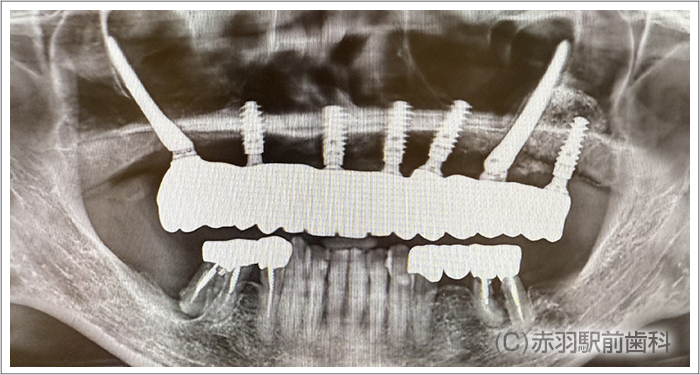

歯を全て失った患者様です。上下とも総入れ歯を入れていました。入れ歯が安定しないので食べるものも制限され会話もしづらい状態です。

CTデータから事前に3Dプリンターで、患者様の実寸代の顎骨模型を作成しておいて手術前にシミュレーションで担当医がインプラント埋入とSRAアバットを装着しておきました。画像は下顎の模型です。両サイドのインプラントはオールオン4特有の傾斜埋入をしてあります。

シミュレーション通りの位置にインプラント手術を完了しました。上下ともに両サイドのインプラントはオールオン4特有の傾斜埋入をしています。

インプラント手術完了後にSRAアバットを装着した状態の口腔内です。固定式の仮歯が当日に入ります。

上下に最終的な上部構造の人工歯をスクリュー固定した状態です。内部の見えない部分をチタンフレームで補強して歯肉をハイブリットセラミックで加工。人工歯はジルコニアの歯を1本ずつ仕上げて完成しました。

実際に笑った時の口元です。人工歯肉の付け根は、唇の内側に隠れて見えないように計算して治療していますので、インプラントだとは他人からは判別できないです。